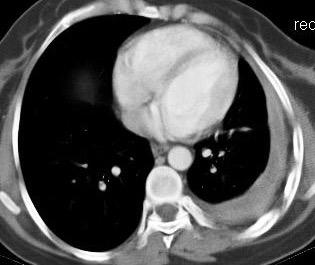

Síndrome de afectación postcardiaca (postcardiac injury)

Post infarto 1-7 % (Dressler)

Trauma cerrado Implantación marcapasos

Cirugía cardiaca. 17-31% (Post.pericardiotomía)

3707 pacientes 29 Derrames (0,78%) > de 25% del hemitórax

Todas menos 2 Izdos.

Angioplastia

By-pass coronario 21-10-03